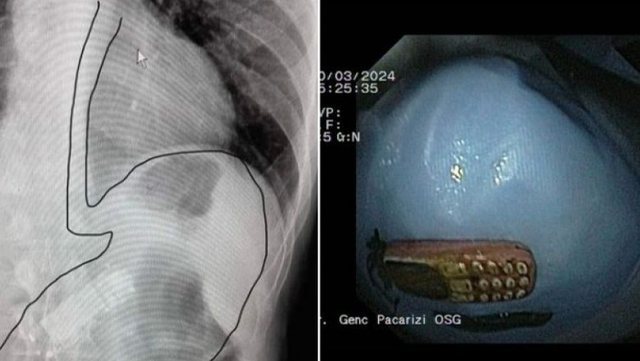

Një ngjarje e pazakintë është regjistruar në Malishevë ku brenda stomakut të një pacienti është gjetur dhe nxjerr një telefon. Rastim e kanë konfirmuar për mes një postimi Ordicanaca OSG ku ka ndarë edhe foto.

Më tej në njoftim bëhet me dije se pacienti që po trajtohej për çrregullime depresive dhe është dërguar nga familjaret në një klinikë në Malishevë. Pas vizitave mjekët kanë gjetur në stomakun e tij një telefon. Përmes një ndërhyrjeje mjekët kanë bërë të mundur heqjne e objektit nga stomaku.

“Pacienti NN, me çrregullime depresive, duke u trajtuar për sëmundje të varshmërisë, sillet nga familjaret ne ordinancën OSG ne Malishevë me ç’rast dhe i largohet trupi i huaj nga lukthi, me endoskop fleksibil duke manovruar me aksesoret përkatës, me asistim te Dr. Taulant Kryeziu, infermiere Florida Shala, procedura kryhet me sukses pa komplikime! Pacienti referohet për trajtim te mëtejshëm tek psikiatri”, thuhet në postimin e Ordinancës OSG.